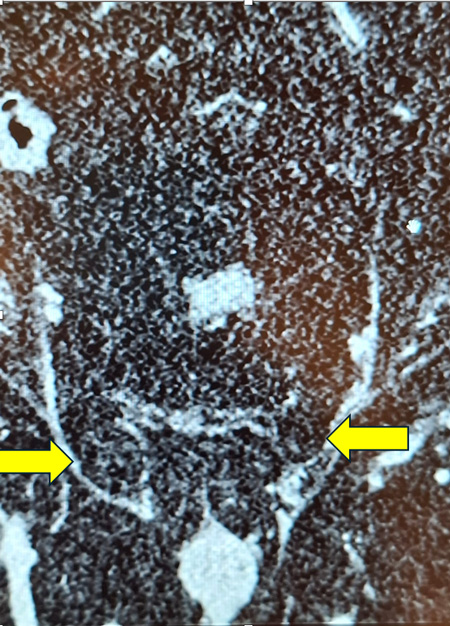

CT scan (coronal image) showing groin hernias on both sides in a man

Sometimes the diagnosis is quite obvious and no tests or scans are required. Sometimes an ultrasound scan may be required. Alternatively, a CT or MRI scan may also provide the answer.